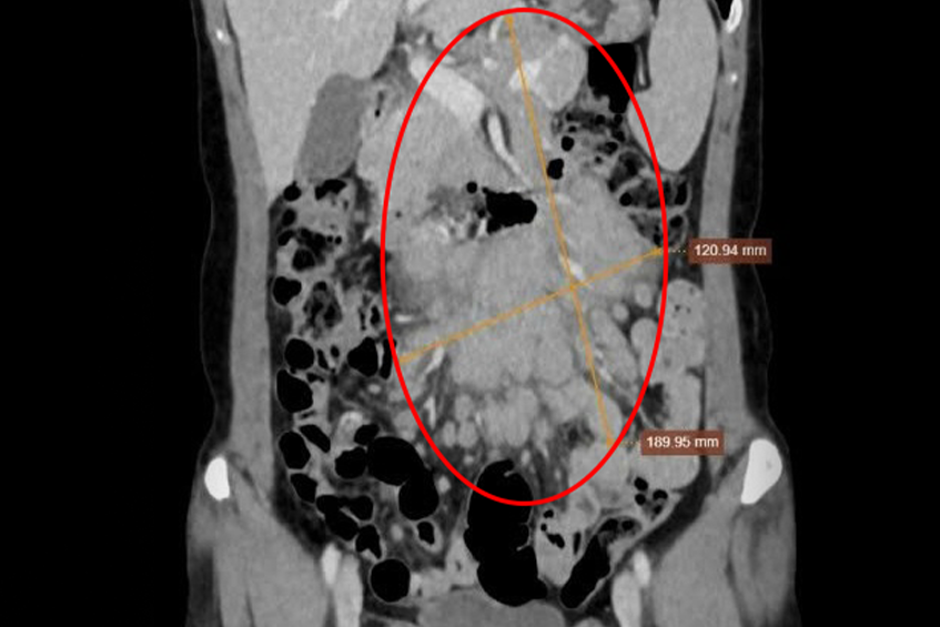

Lien first noticed a lump on the left side of her neck in October of last year. Experiencing frequent abdominal pain recently, she sought treatment at Tam Anh General Hospital in Ho Chi Minh City. A CT scan revealed dozens of lymph nodes clustered together, measuring 12x19 cm, pressing against her intestines. A biopsy of the neck lymph node and bone marrow confirmed a diagnosis of stage 4 malignant lymphoma (lymphatic cancer).

Lien's CT scan shows clusters of lymph nodes, ranging from tiny to large, in her abdomen. Photo: *Tam Anh General Hospital*